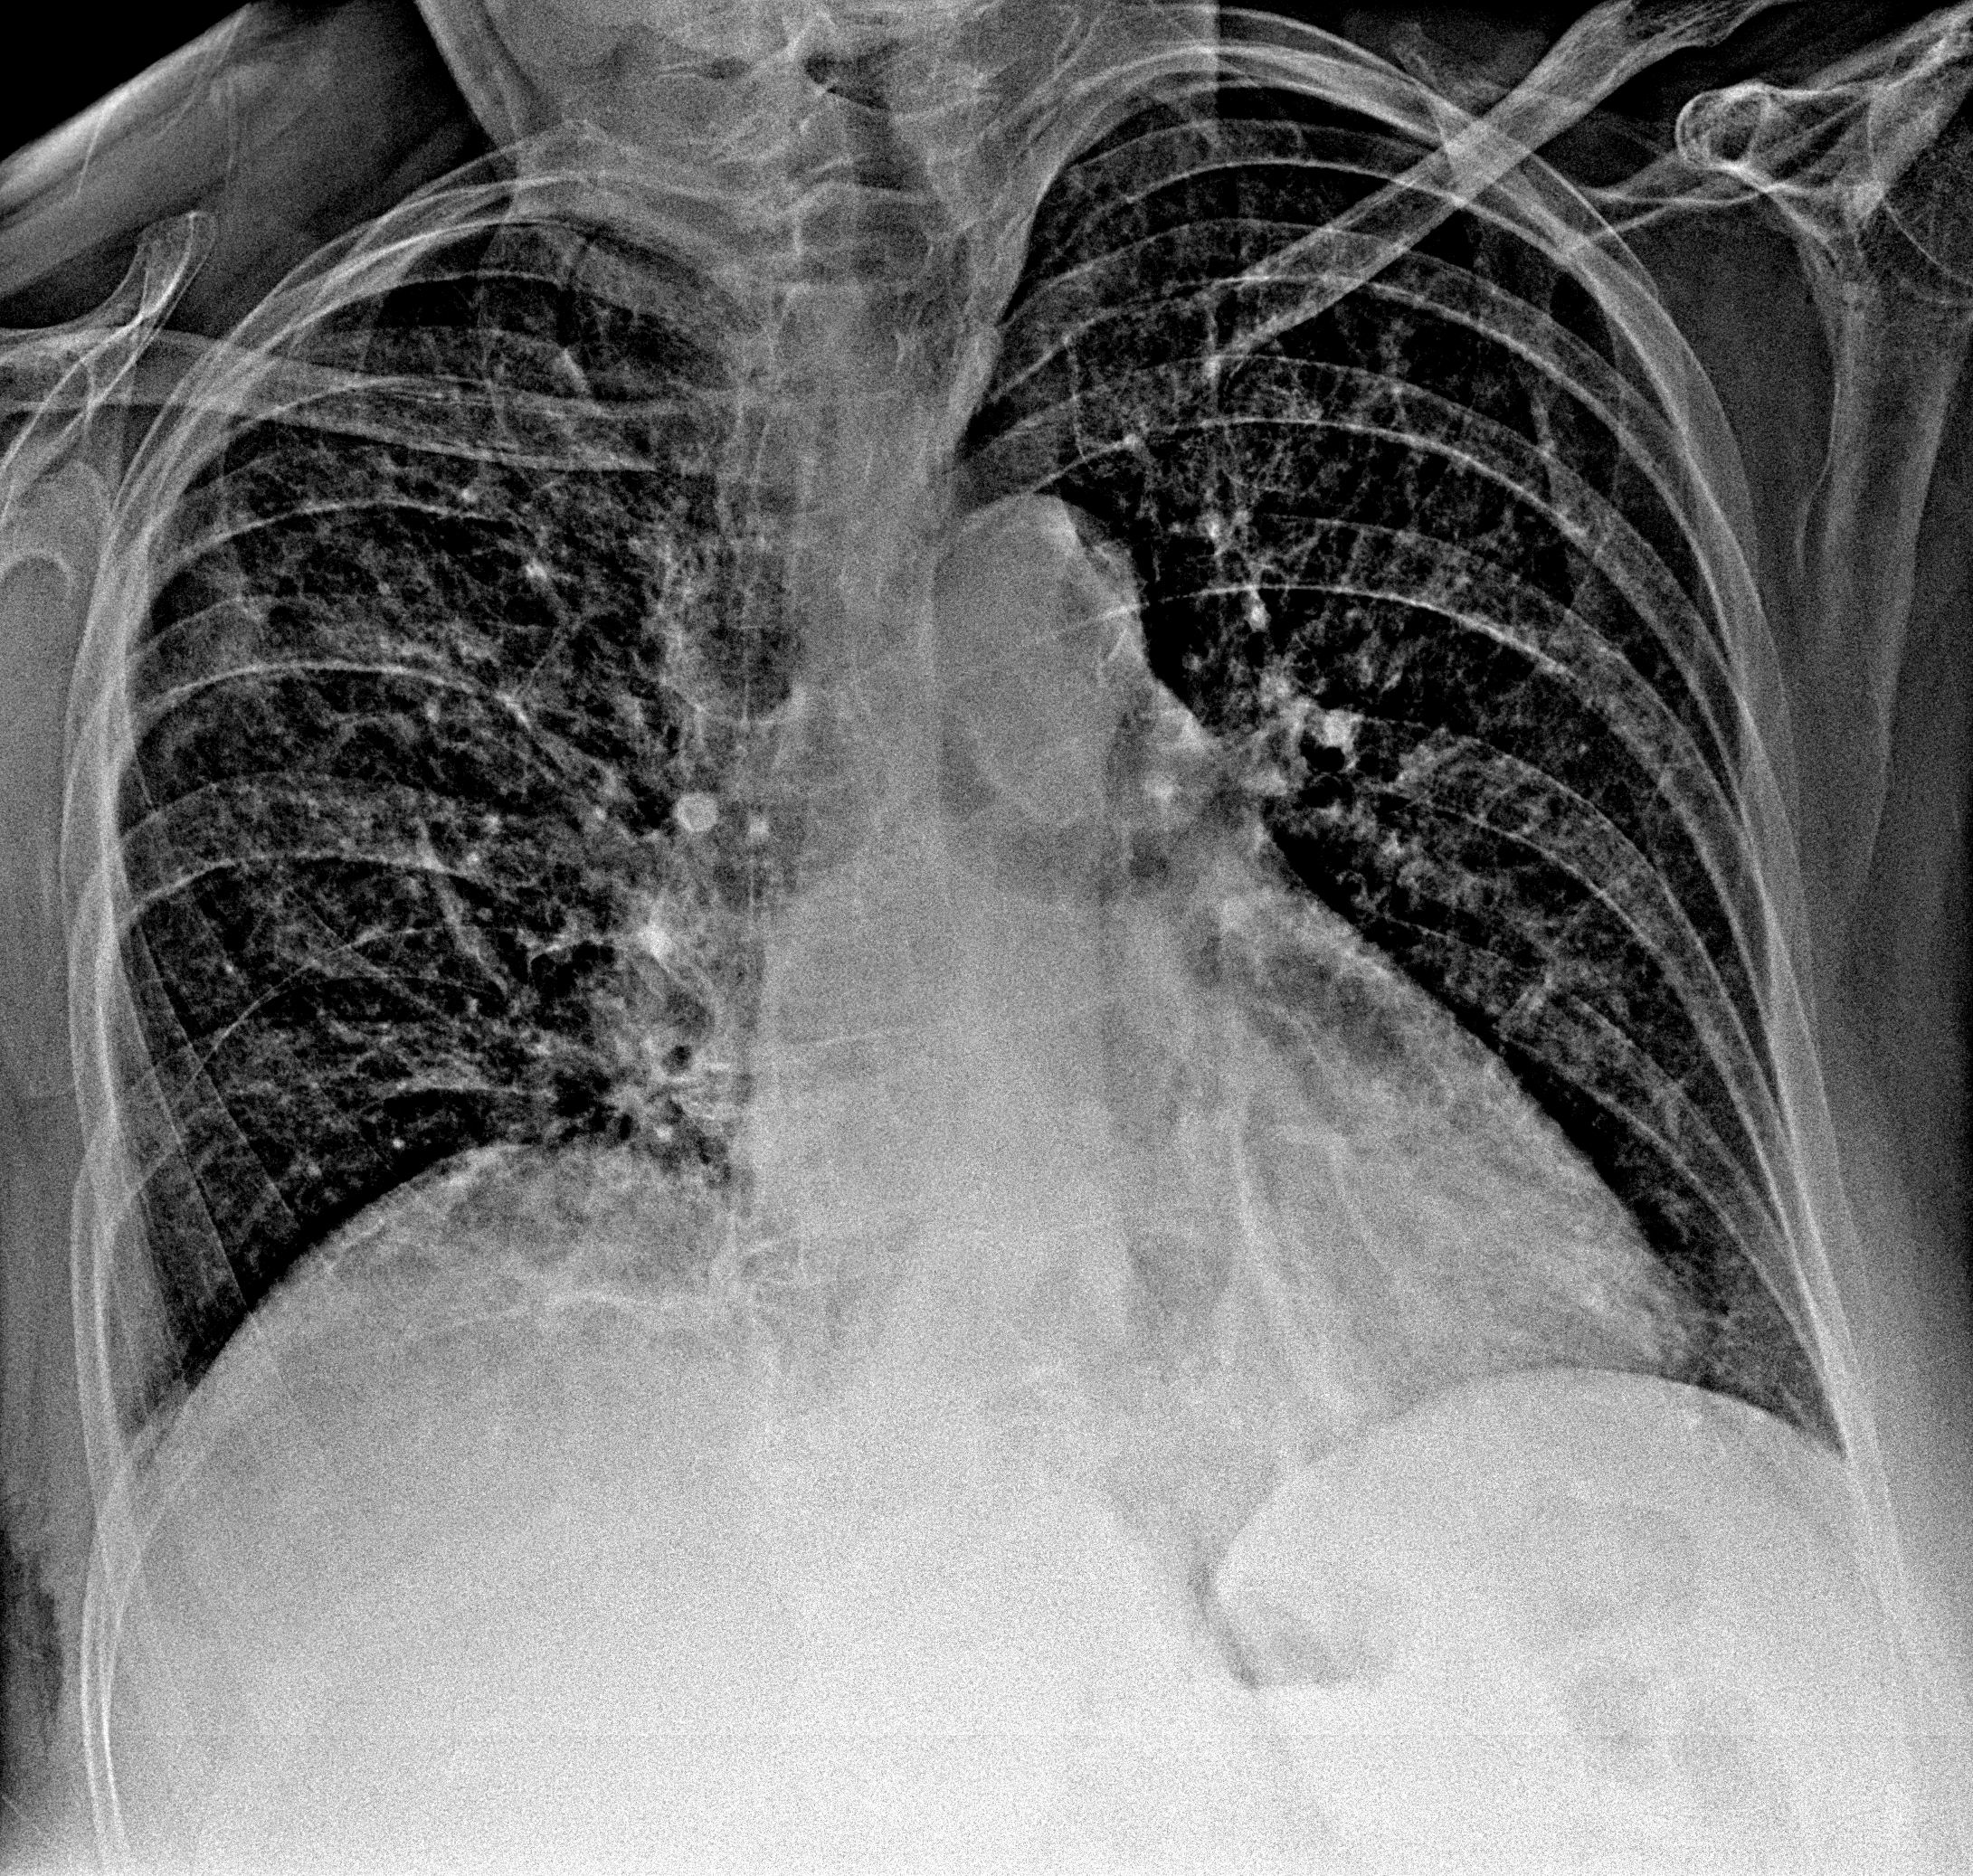

Пневмония

при переломе шейки бедра и пневмонии от компании МосРентген Центр - партнера Института имени Склифосовского